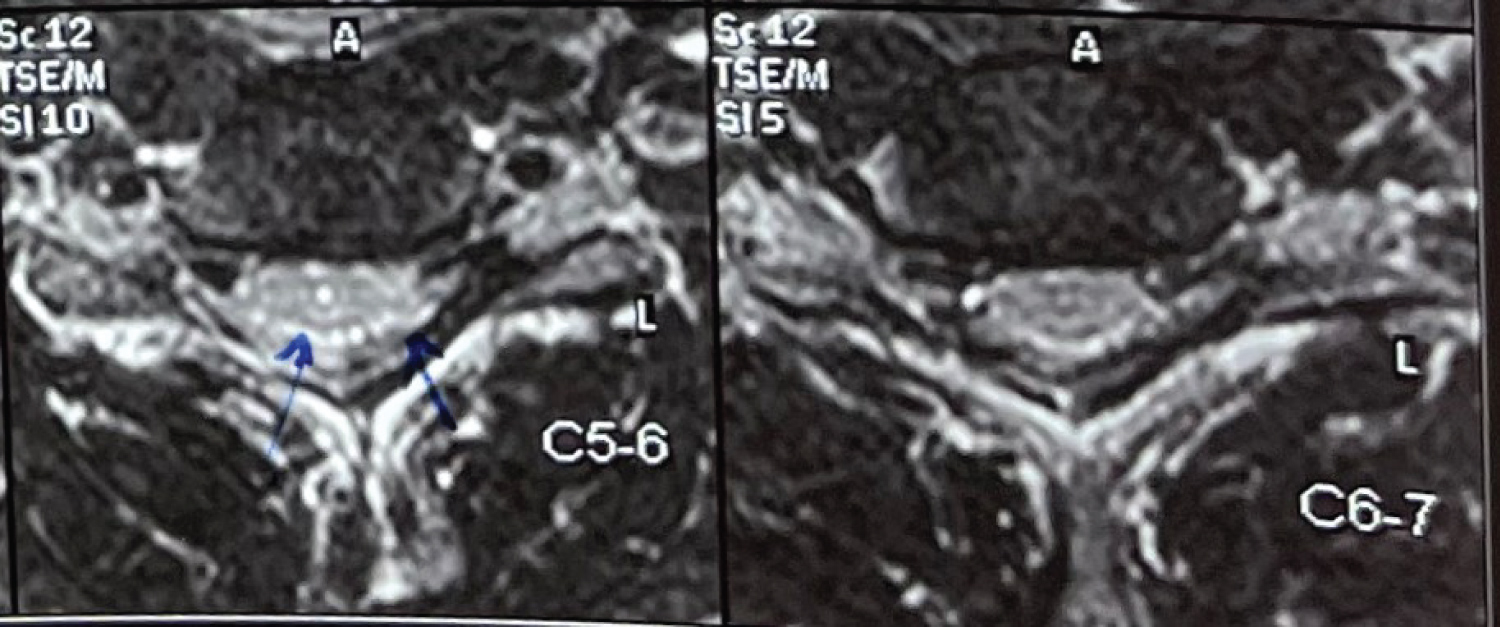

A twenty-one-year-old male right-handed came to us with a chief complaint of weakness in the grip of both hands (right > left) which was noticed by him in August 2020 when he was gathering clay with his bare hands to make a Ganesha idol. He experienced that this weakness was static and non-progressive and was not related to any aggravating or relieving factors. The patient also had a history of occasional tingling in both of his hands since childhood which was left unattended. The patient started noticing the loss of the bulk of his bilateral hand muscles. The patient did not have weakness in proximal upper limbs or any of the lower limbs. He did not have any complaints regarding bowel and bladder habits. On examination, we found wasting of thenar as well as hypothenar muscles (Figure 1 and Figure 2). The patient had asymmetric weakness in all his intrinsic muscles (3/5) of both hands. All the sensations were well preserved and deep tendon reflexes were normal. The nerve conduction studies, and EMG findings were suggestive of bilateral C8-T1>>C7>>C5-C6 very chronic motor axon degeneration with the site of involvement likely to be at anterior horn cell or cord level. His MRI of the cervical spine (Figure 3, Figure 4 and Figure 5) was showing focal atrophy of the lower cervical spinal cord from C5-C6 to C6-C7 disc levels with mild prominence of the central canal and on flexion, there was the ventral movement of posterior dura with the prominence of the posterior epidural venous plexi extending from C3 to upper dorsal levels. All these findings were suggestive of Hirayama disease. The patient was advised to wear a cervical collar and on follow up after two months he had relief from his tingling and there was an improvement in power (4/5) of intrinsic muscles of both hands. He was able to write in reasonably good handwriting and was able to perform all his routine activities without any disturbances.

Figure 5: Axial T2 images showing asymmetric cord atrophy and hyperintense signal in the anterior horn cell region. View Figure 5